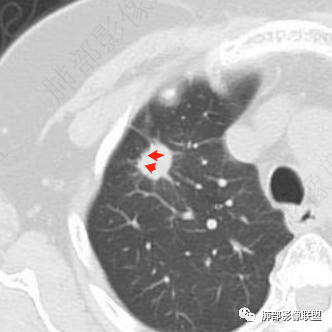

右肺上叶结节看着就挺恶的,血管集束、冠状位看到一条血管弯曲,可疑空泡,周围似乎有磨玻璃?(需要薄层明确),这些征象支持腺癌。但是病灶比较明显的延迟强化、环形强化,毛刺比较长且收缩力不是太明显,炎性肉芽肿还是要考虑。

右肺上叶前段孤立性实性结节,不均匀明显延迟强化,形态不规则,位于胸膜侧见小锯齿状凸起,胸膜牵拉及兔耳侧,结节内上侧见磨破璃影,边清(需薄层确认),另见血进入结节,邻近血管集束征,结节外侧见指状凸起影(恶性多见),定恶性,腺Ca;鉴别炎性肉芽肿,结合肺肿瘤指标抗原检查,经皮肺穿刺活检!

老年女性,体检发现,无呼吸道症状。右肺上叶尖段孤立性实性结节,下份见空泡,余密度较均匀。病灶形态不规则,边缘多膨隆,可见浅分叶及细毛刺,血管集束,未能显示相关支气管情况。病灶胸膜侧见小锯齿状凸起、胸膜牵拉及兔耳征,结节前缘见磨玻璃影,磨玻璃影边界较清楚(需薄层确认),结节外侧见指状凸起影。未见卫星病灶,纵隔窗未见明显钙化。增强扫描:较明显渐进性强化。

浸润性腺癌支持点还有空泡及磨玻璃晕,但非薄层图像,磨玻璃影表现可靠性降低。